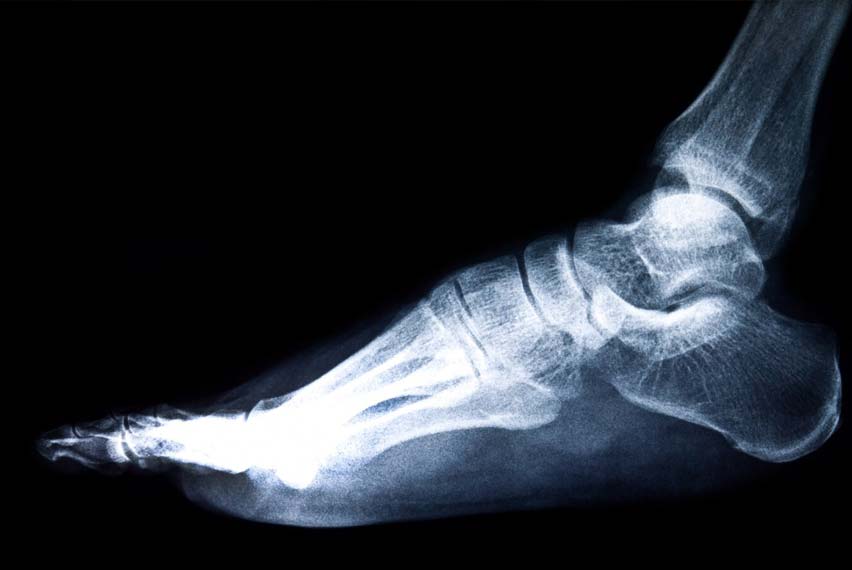

Ayak bileği artroskopisi, ayak bileği doku ve eklemindeki sorunları teşhis ve tedavi etmek için kullanılan minimal invaziv bir cerrahidir.

Ayak Bileği Artroskopisi Nedir?

Artroskopi, "artro-" (eklem) ve "-skopi" (gözlemleme) kelimelerinden türetilmiş bir terimdir. Ayak bileği artroskopisi, eklem içindeki sorunları görüntüleyip tedavi etmek için endoskopik bir kameranın ve küçük cerrahi aletlerin kullanıldığı bir işlemdir. Eklemdeki doku, kıkırdak ve bağ yapılarının doğrudan gözlemlenmesine olanak tanır ve hasar gören yapıların onarılmasını sağlar. Bu teknik, açık cerrahiden daha az doku hasarı yarattığından, hem hasta konforu açısından hem de iyileşme süresi açısından avantaj sağlar.